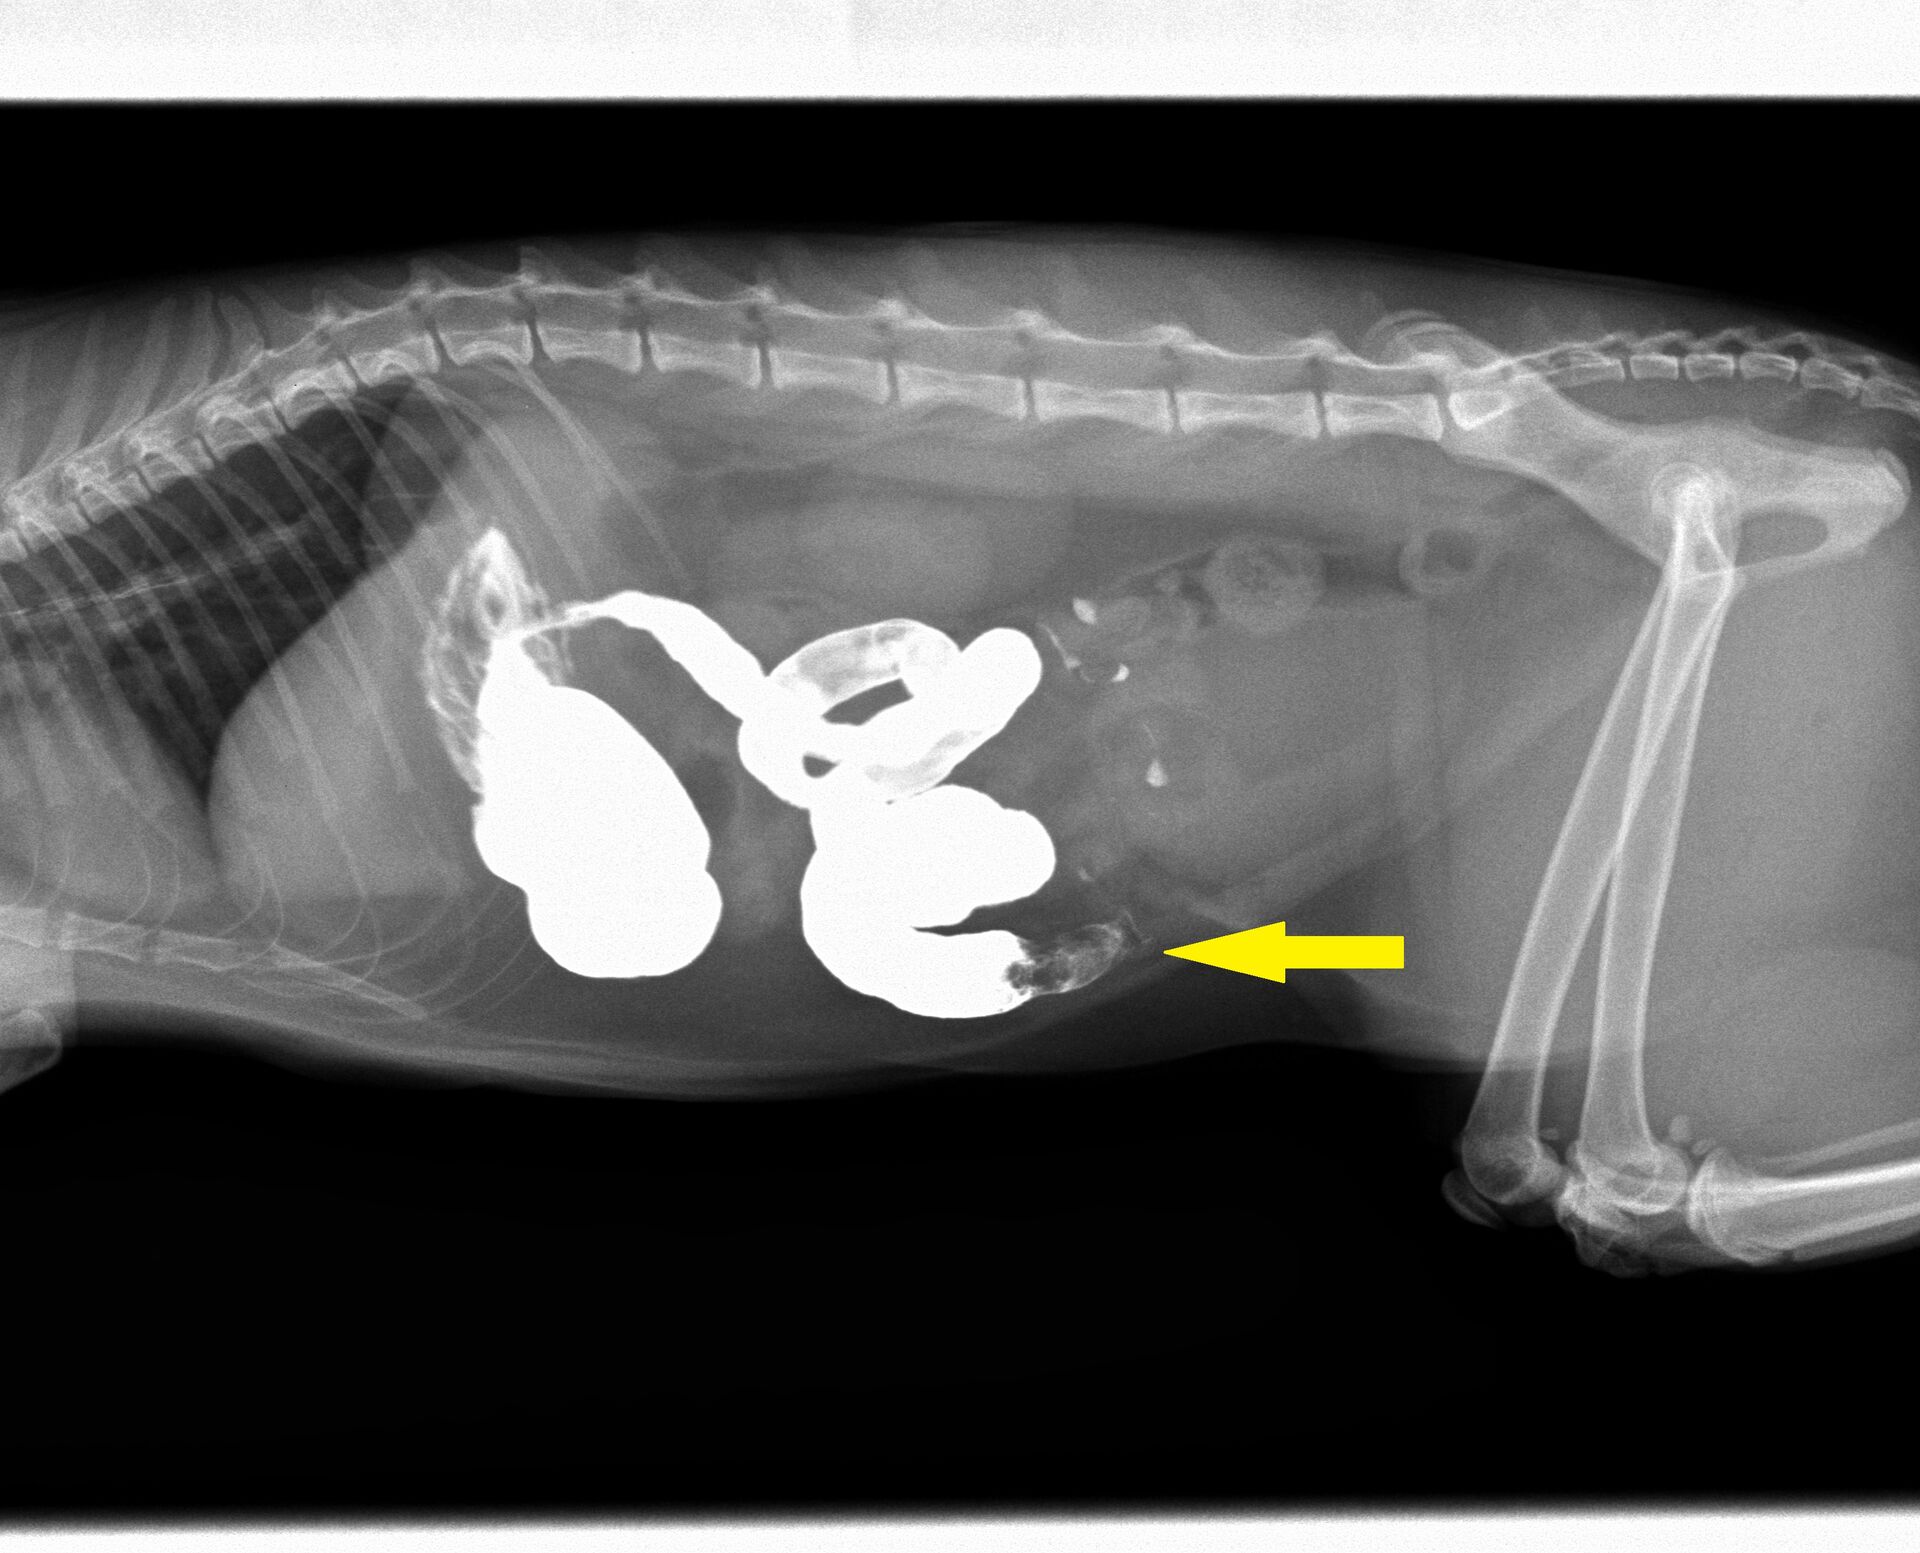

ところが、翌日また来院され、状態は全く変わらず、相変わらず食欲がなく、茶色のものを吐くようになったということでした。このことから腸閉塞を疑い、バリウム検査を行いました。バリウムを飲ませてから4時間目のレントゲンが下の写真ですが、小腸のある場所(黄色矢印)でバリウムが止まってしまい、それ以降は流れていません。胃内はバリウムで満たされています。通常は2-3時間で胃の中のバリウムはほとんどが流れ出てしまいます。